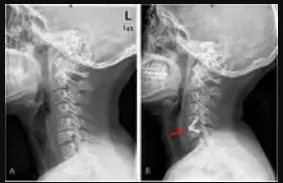

Revision Spine Surgery Edison